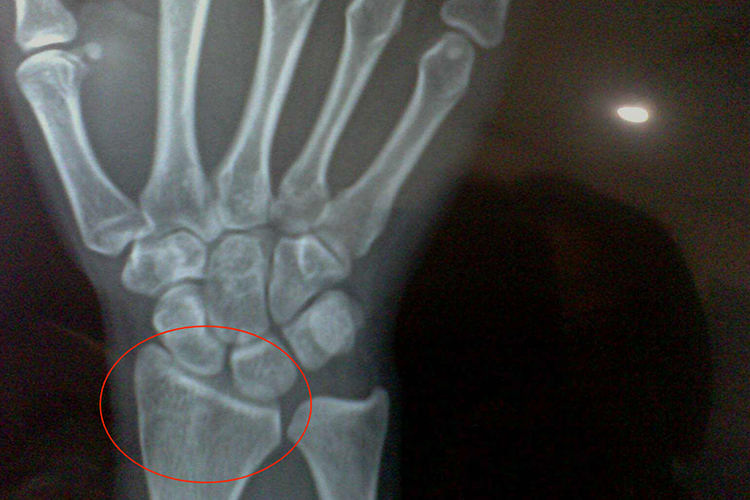

正常情况下手腕骨骺闭合前处于儿童期及儿童期之前,此时骨骼关节仍处于生长阶段,手腕的骺软骨中心出现二次骨化中心,X线表现为小点状致密影,显影呈透明带,称为骨骺板,此时没有骨骺线形成。

骨骼生长期后手腕骨骺逐渐闭合,二次骨化中心逐渐增大形成骨松质,边缘也逐渐变光整,最后与骨干愈合,X线显示骨骺板逐渐变窄呈透亮线,称为骨骺线,最终消失。

继发骨化中心及其周围的软骨称为骨骺,与其相连的长骨端称为干骺端,骨骺与干骺端之间生长最活跃的区域为骨骺板。在生长过程中骨骺与干骺端闭合,骨骺板消失或残留一致密的带状骨骺线。骨化中心出现和闭合的时间称为骨龄。儿童的骨骼由骨干、干骺端、骨骺板、骨骺组成。骨骺如有多个骨化中心,则先彼此融合,然后再与干骺端融合。